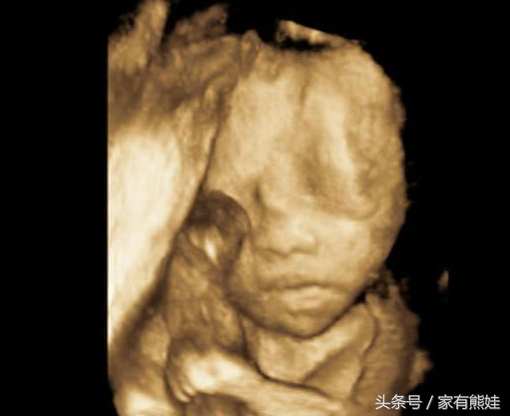

时间过的好快,一下子就37W了,现在好像知道自己肚肚里的是男宝还是女宝,JMM来看过之后猜猜看,也上就要揭晓答案了哦~

孕期特征罗列如下: